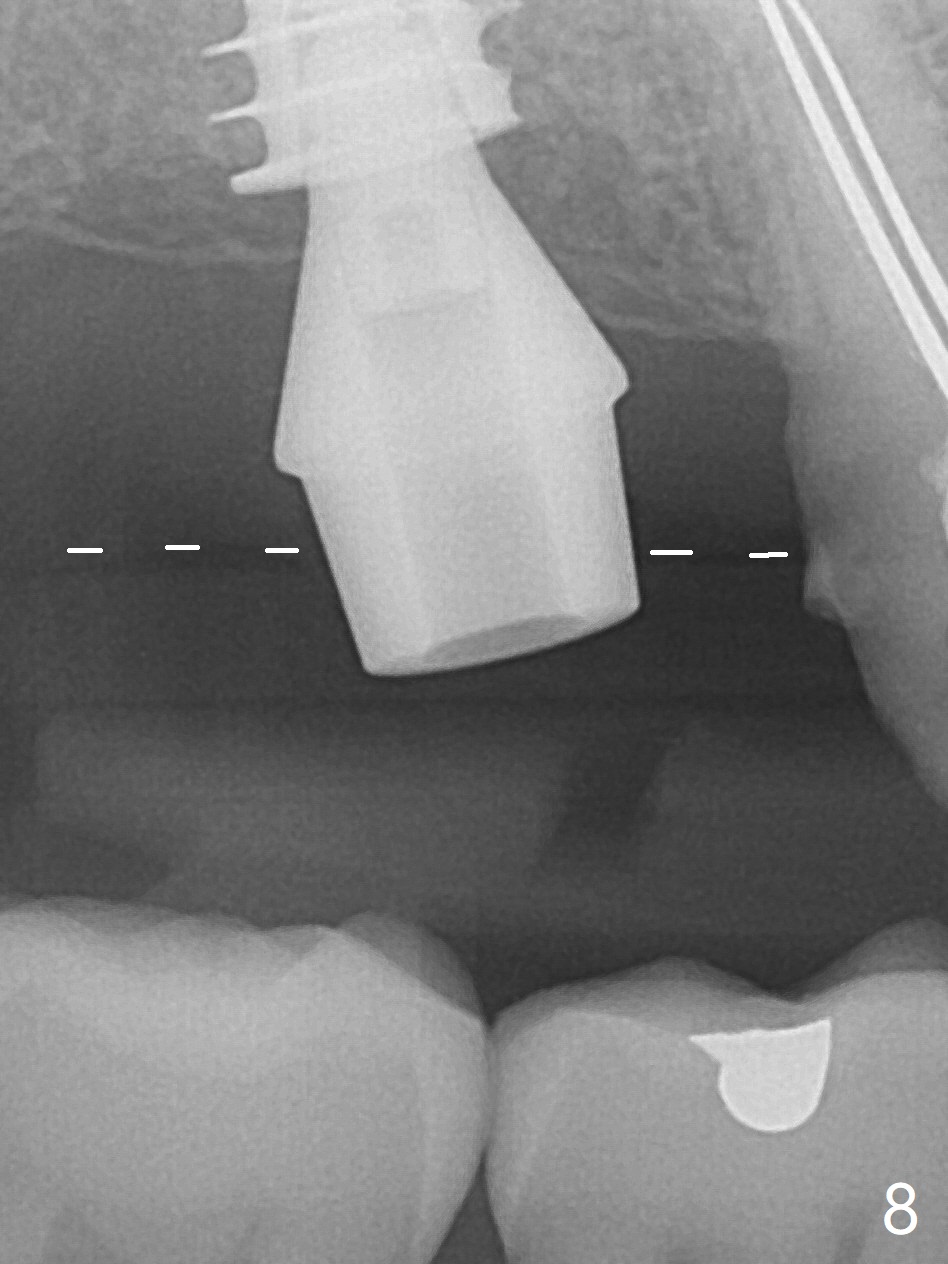

Since the ridge is wide at the site of #2, Magic Split is used for access (flapless) and bone expansion. The bone is so soft that there is no resistance until 4.3 mm Magic Expander is used for 9 mm (Fig.6). A 5 mm tap drill is stable (Fig.1), so are a 5.5x9 mm dummy implant (Fig.2) and a 6x9 mm IBS implant (Fig.3 (<: sinus lift)). In fact the distal thread is still supracrestal (Fig.4 (BW)). After additional 2 mm placement, the distal thread is subcrestal (Fig.5); the mesial margin of a 6.5x4(4) mm abutment is subgingival. A longer cuff (5 mm instead of 4 mm) is more favorable for future restoration. At present the abutment (Fig.7) as well as the tooth #3 with rugged surfaces is used to hold periodontal dressing in place. The abutment margin is completely subgingival 3 months postop (Fig.8 (white dashed line: gingival margin)). It appears that the implant is placed ~ 1 mm deeper than ideal (Fig.9). Diode laser is used for gingivectomy prior to impression. The abutment screw becomes loose 2 months post cementation. After retightening, occlusal equilibrium is conducted with 3 layers of articulating paper. Night guard is provided. The crown/abutment dislodges 1 year 2 months later. Since the gingiva is erythematous, a 6x7 mm healing abutment is placed (Fig.10). The implant seems to have been placed too deep and palatal. It appears that an abutment driver should be buried to prevent the screw re-loosening. Guided surgery should have been done.